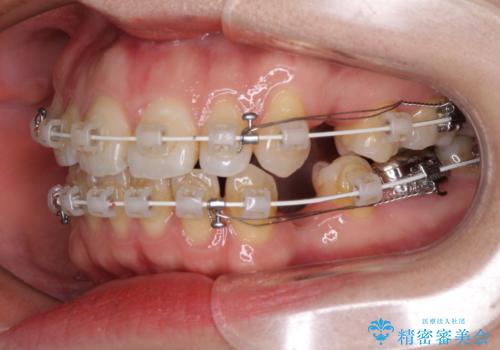

- 矯正装置

- 審美装置

- 唇の閉じにくさを気にして来院された患者様です。

上下左右第一小臼歯4本を抜歯し、ワイヤー装置にて口元を引っ込めるよう矯正治療を行うこととしました。

骨格的に下顎がやや前方にあるため、横顔のシルエットが著しく変化することはありませんでしたが、口元はスッキリと引っ込み、唇が閉じやすくなりました。